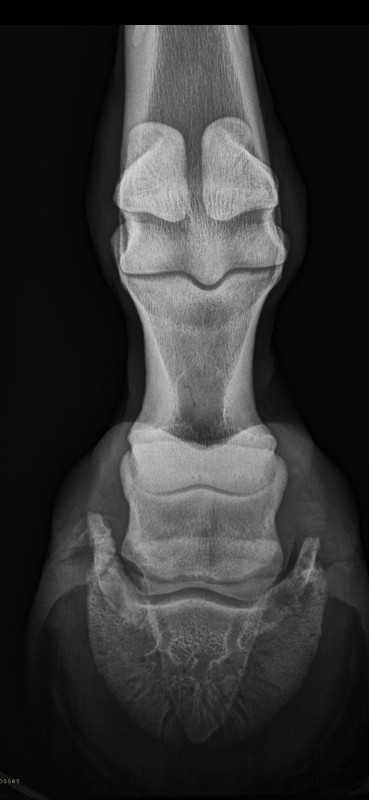

Hier , j'ai fait faire une radio de contrôle via un appareil portatif qui comportait un appareil radio (face pied) et une plaque à placer au dos du pied (celui-ci était placé sur une cale en bois inclinée et je devais garder une tension sur le canon pour garder la position).

Mon soucis est que je ne sais pas dire si la radio est une vue de face ou une vue de dos (onde rebondit sur la plaque et traverse le pied des glaumes vers la pince ?).

Une photo faite de derrière il y a 6 mois à la clinique où l'on voit la fêlure/fracture de la forme (cartilage ungulaire) extérieur de l'antérieur gauche.

La seconde photo pour laquelle je pose ma question.

Objectif : savoir si mon cheval est guéri après 6 mois d'arrêt et recommencer le travail.

Selon lui la zone calcifiée est de nouveau entourée de cartilage donc que du positif.